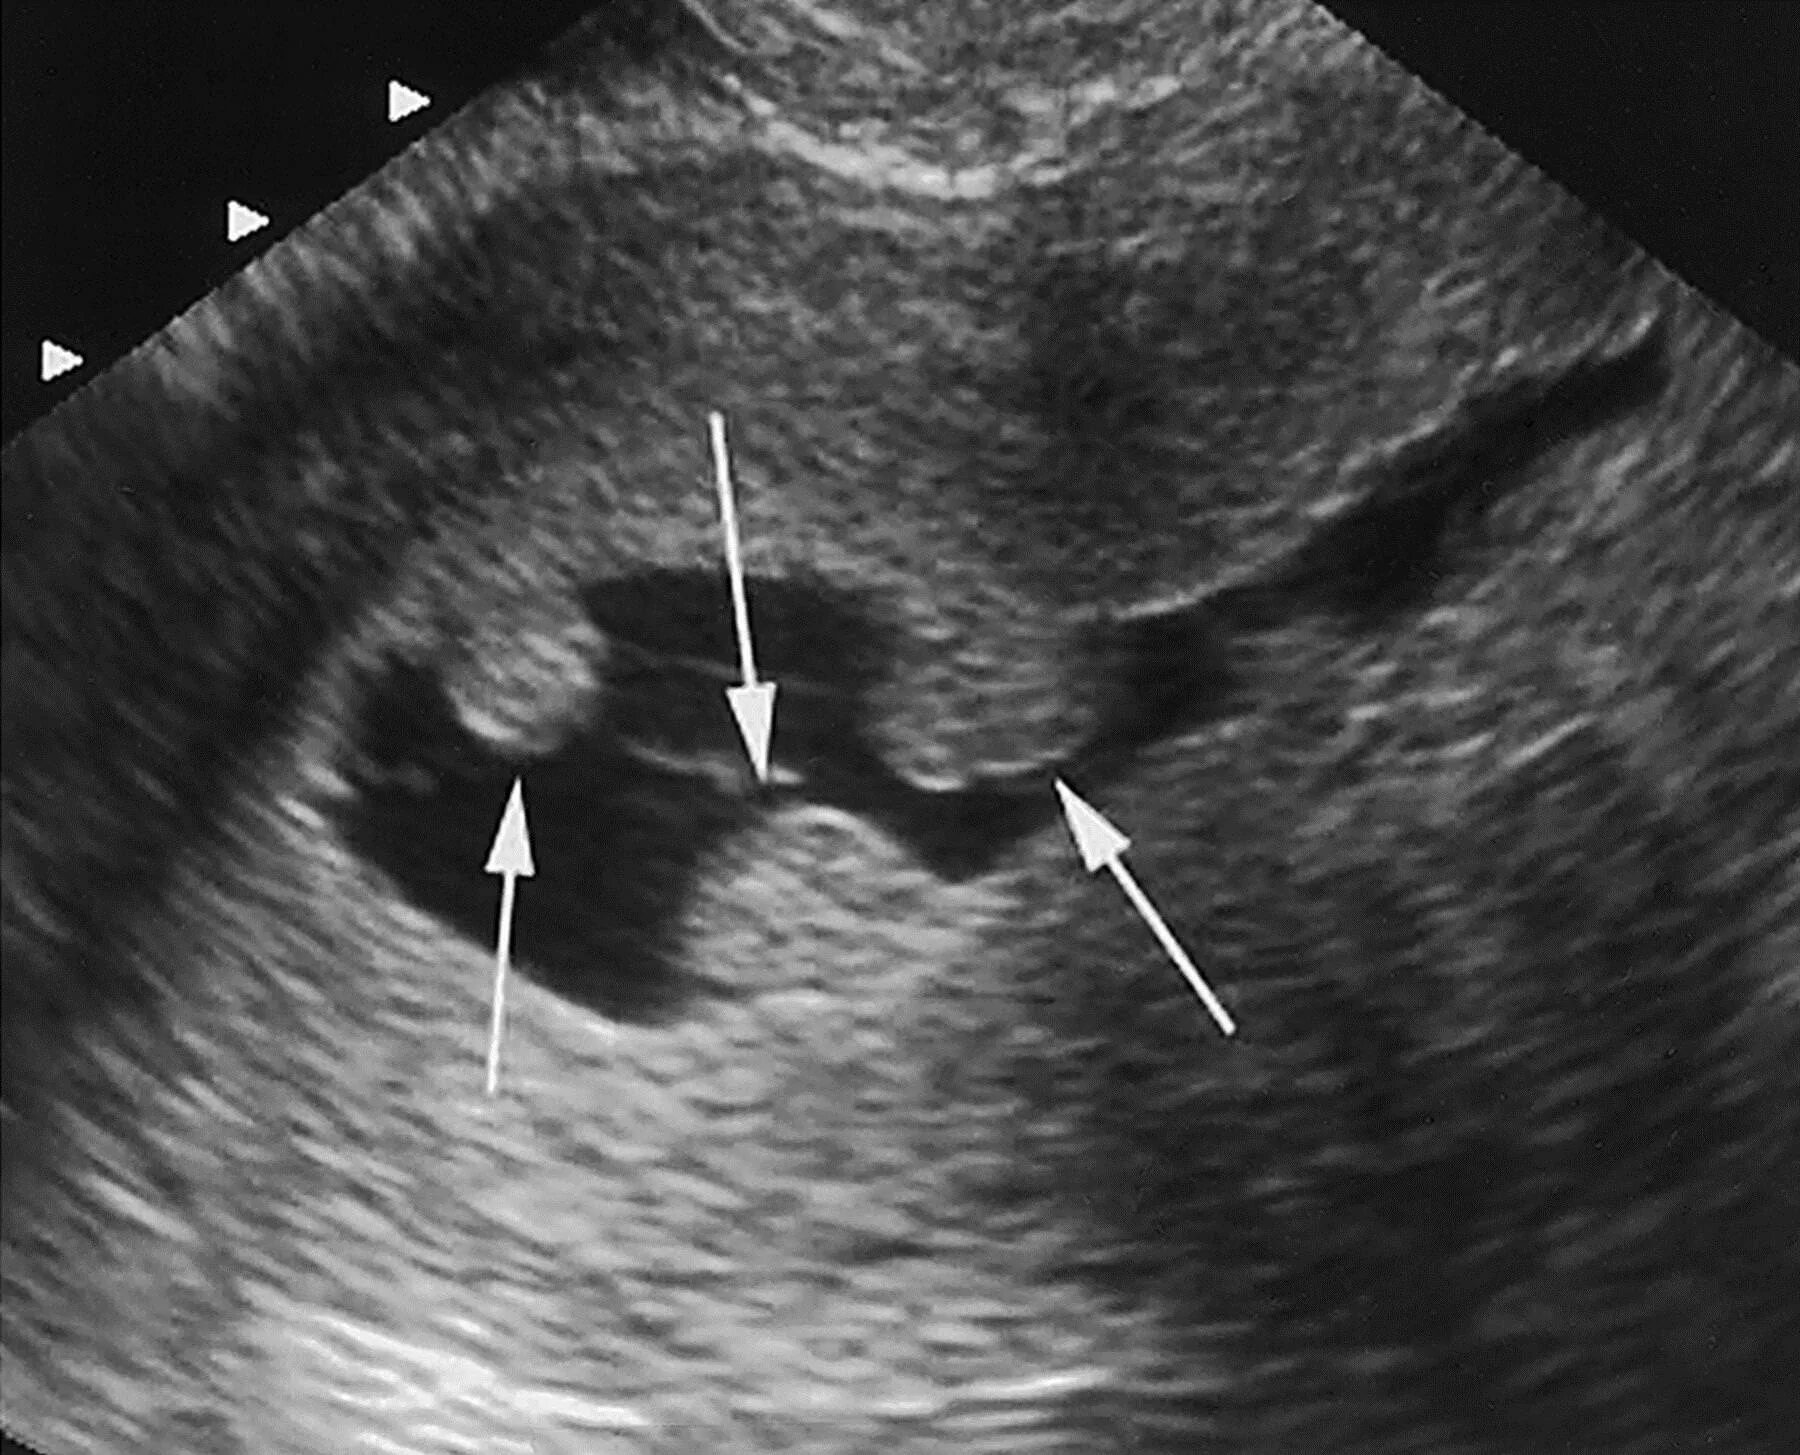

Эндометрия матки причины возникновения